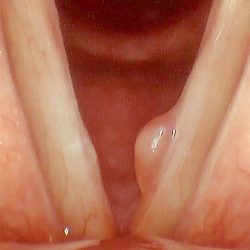

Vocal polyp

Vocal polyps are non-cancerous growths that develop on the vocal cords. They typically occur as a result of vocal abuse or injury, such as chronic throat clearing, yelling, or singing improperly. Symptoms of vocal polyps may include hoarseness, a breathy or weak voice, a lump or swelling in the throat, and difficulty speaking or singing. Treatment options for vocal polyps may include voice therapy, vocal rest, and in some cases, surgery to remove the polyp. It is important to address vocal polyps promptly, as they can worsen over time and potentially lead to permanent vocal damage if left untreated.

Voice assessment

Voice assessment in ENT involves the evaluation of a patient’s vocal function to diagnose and treat various voice disorders. The assessment typically begins with a comprehensive medical history and physical examination of the patient’s larynx and vocal cords. Additional tests may include acoustic analysis of the voice, which measures factors such as pitch, loudness, and vocal quality, as well as perceptual analysis, which evaluates the listener’s subjective impression of the voice. Other specialized tests such as laryngoscopy or stroboscopy may also be used to visualize the vocal cords during speech or singing. Based on the results of the assessment, the ENT specialist can develop an individualized treatment plan, which may include voice therapy, medication, or surgical intervention.